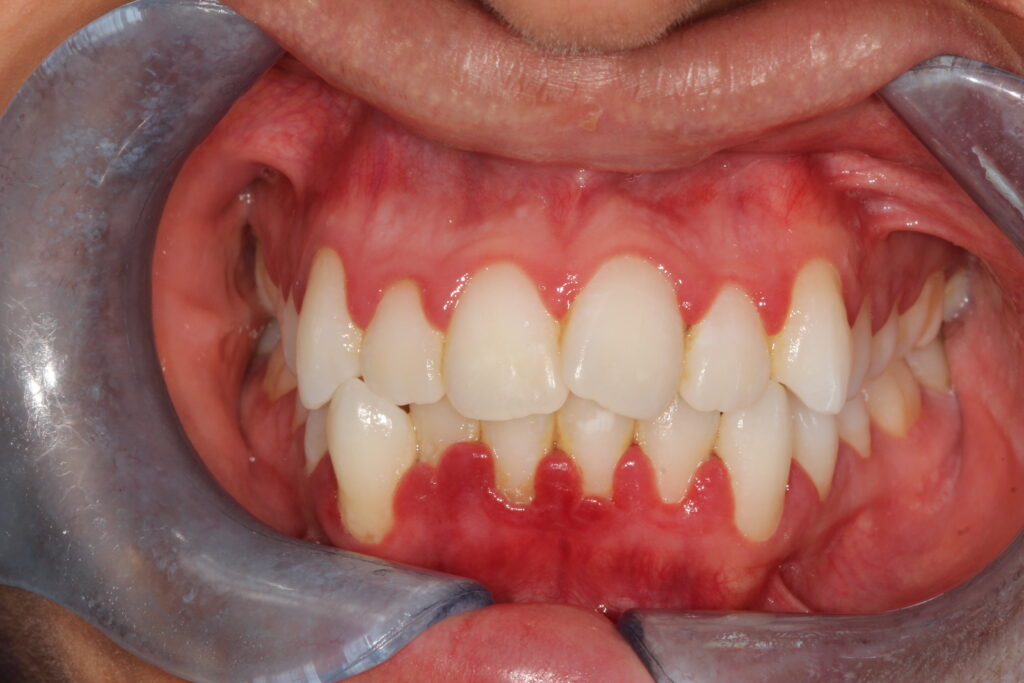

Smile Gallery

Brighten your smile, lift your confidence.

This gallery showcases real results at Goldsworth Road Dental & Implant Centre achieved with Air Polishing designed to look beautifully natural.

after hygiene

Before hygiene

Before

After